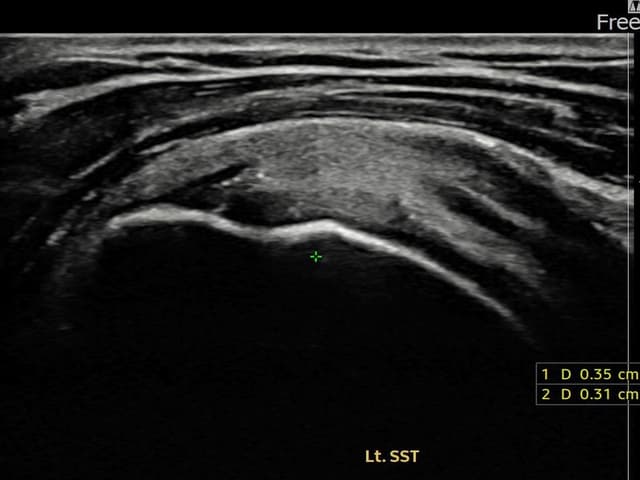

[촬영시기:24.01.25~24.04.03]

[어깨인대 축소봉합술] 좌측 어깨 부착부 통증과 야간 통증으로 수면 장애가 있어 내원하셨습니다.